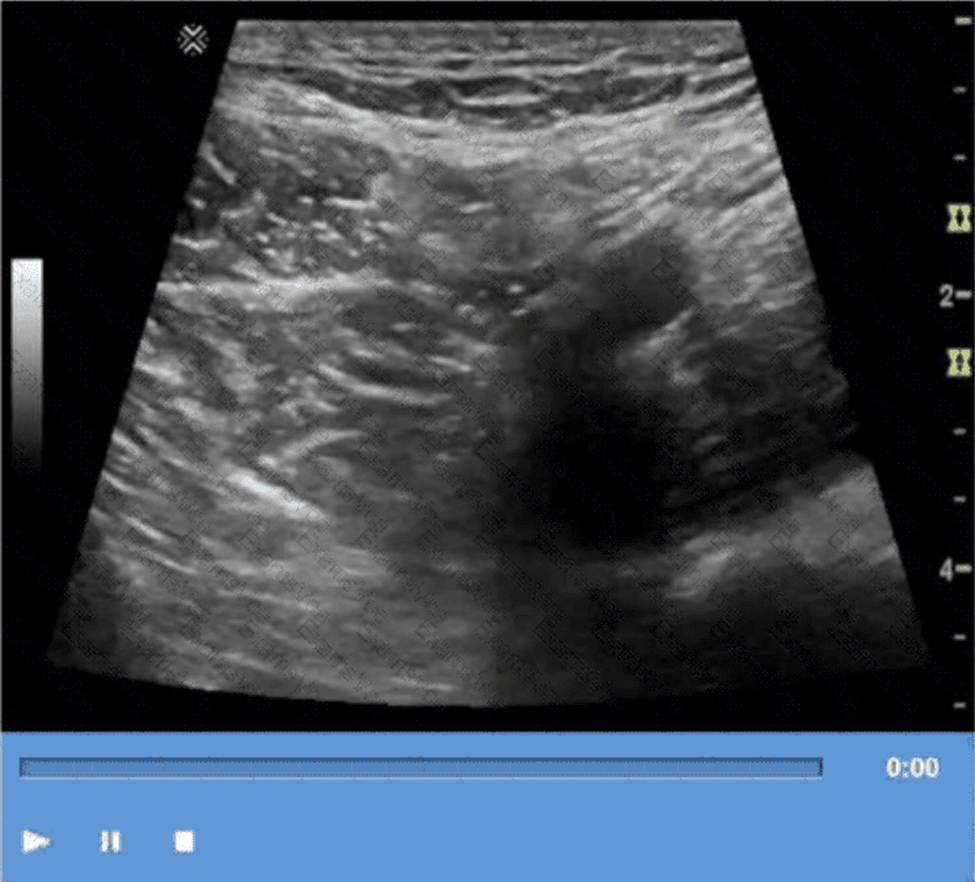

Question No : 15

Based on this image, what is the most likely clinical indication for the examination?

The ultrasound image demonstrates findings consistent with hypertrophic pyloric stenosis (HPS). This condition typically affects infants between 2 and 8 weeks of age and presents clinically with non-bilious projectile vomiting, weight loss, and dehydration.

In the ultrasound image, the classic “target” or “donut” sign can be seen in the transverse view of the hypertrophied pyloric muscle.

Key sonographic criteria for HPS include:

Pyloric muscle thickness #3 mm

Pyloric channel length #15C18 mm

This imaging appearance strongly correlates with the clinical presentation of projectile vomiting (Choice D), which is the hallmark symptom of HPS.

Comparison of answer choices:

A. Abnormal prenatal ultrasound (Choice A) is not typically associated with HPS, which develops postnatally.

B. Neonatal hyperbilirubinemia (Choice B) is not an indication for a pyloric ultrasound and affects liver /biliary imaging.

C. Red currant jelly stools (Choice C) are indicative of intussusception, not HPS.

D. Projectile vomiting (Choice D) is the most common clinical indication leading to an ultrasound exam that reveals HPS.